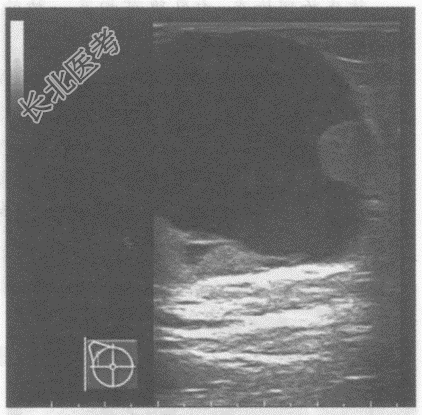

- 单项选择题临床资料:女, 49岁,自诉右乳触及肿物2年余。

临床物理检查: 右乳头外侧可扪及一肿物,质软, 边界清晰。

超声综合描述:右乳头外侧可见4.8cm×4.7cm无回声区, 边界清晰,形态规则, 内可见乳头状中等回声突起。

超声提示: A、右乳腺假体植入

B、右乳腺囊肿

C、右乳腺乳头状囊腺瘤

D、右乳腺脓肿

E、右乳腺脂膜炎